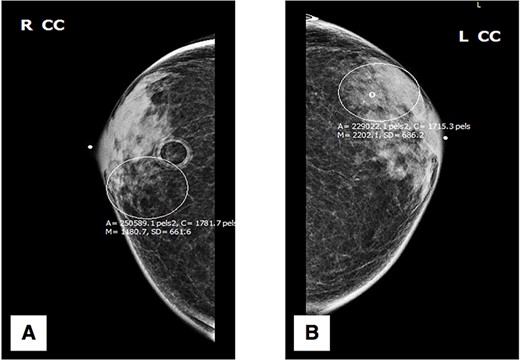

Initial physical exam was notable for bilateral gynecomastia with expression of scant serous fluid on palpation. Negative findings included any ‘active nipple’ discharge, presence of bleeding, breast tenderness, palpable masses or architectural abnormalities. The patient was referred for further diagnostic workup, beginning with digital mammography. Standard craniocaudal (Fig. 1) and mediolateral oblique (Fig. 2) views of bilateral breasts were performed, which revealed pleomorphic calcifications in the upper outer quadrant of the left breast, as well as amorphous calcifications in the lower inner quadrant of the right breast, consequently affording the patient a Breast Imaging Reporting and Data System score of 4 (suspicious for malignancy) with recommendation for subsequent biopsy.

Mediolateral oblique (MLO) mammography: (A) right breast; (B) left breast.